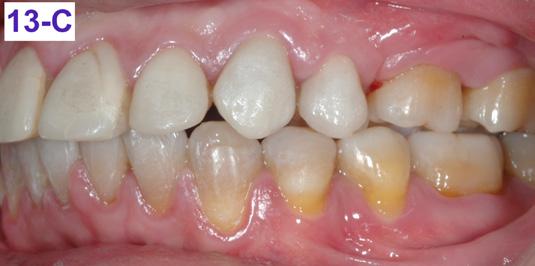

FIG. 13B: Post treatment, right lateral view

FIG. 13C: Post-treatment, left lateral view

Please view the post-treatment images at the time of insertion of the retainers (Figure 13 – A, B, C. D, E, F, G, H, I, J, K, L).